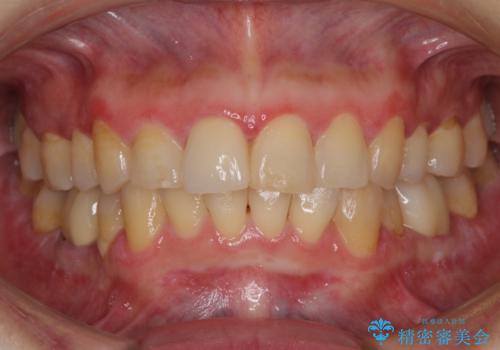

オールセラミッククラウンの治療を行いました。

また、右上の前歯は裏側までヒビが入っていることや、1層構造のラミネートよりも2層構造のオールセラミッククラウンの方が色の再現性も高いことから、右上前歯1本のクラウン治療をおすすめしました。

患者様には大変満足して頂きました。

今回は、歯肉炎があるため、その治療を行ってからクラウンを製作しました。

歯肉炎がない場合は、1か月ほどで治療が完了します。逆に、炎症がひどい場合は、治療期間が長くなります。